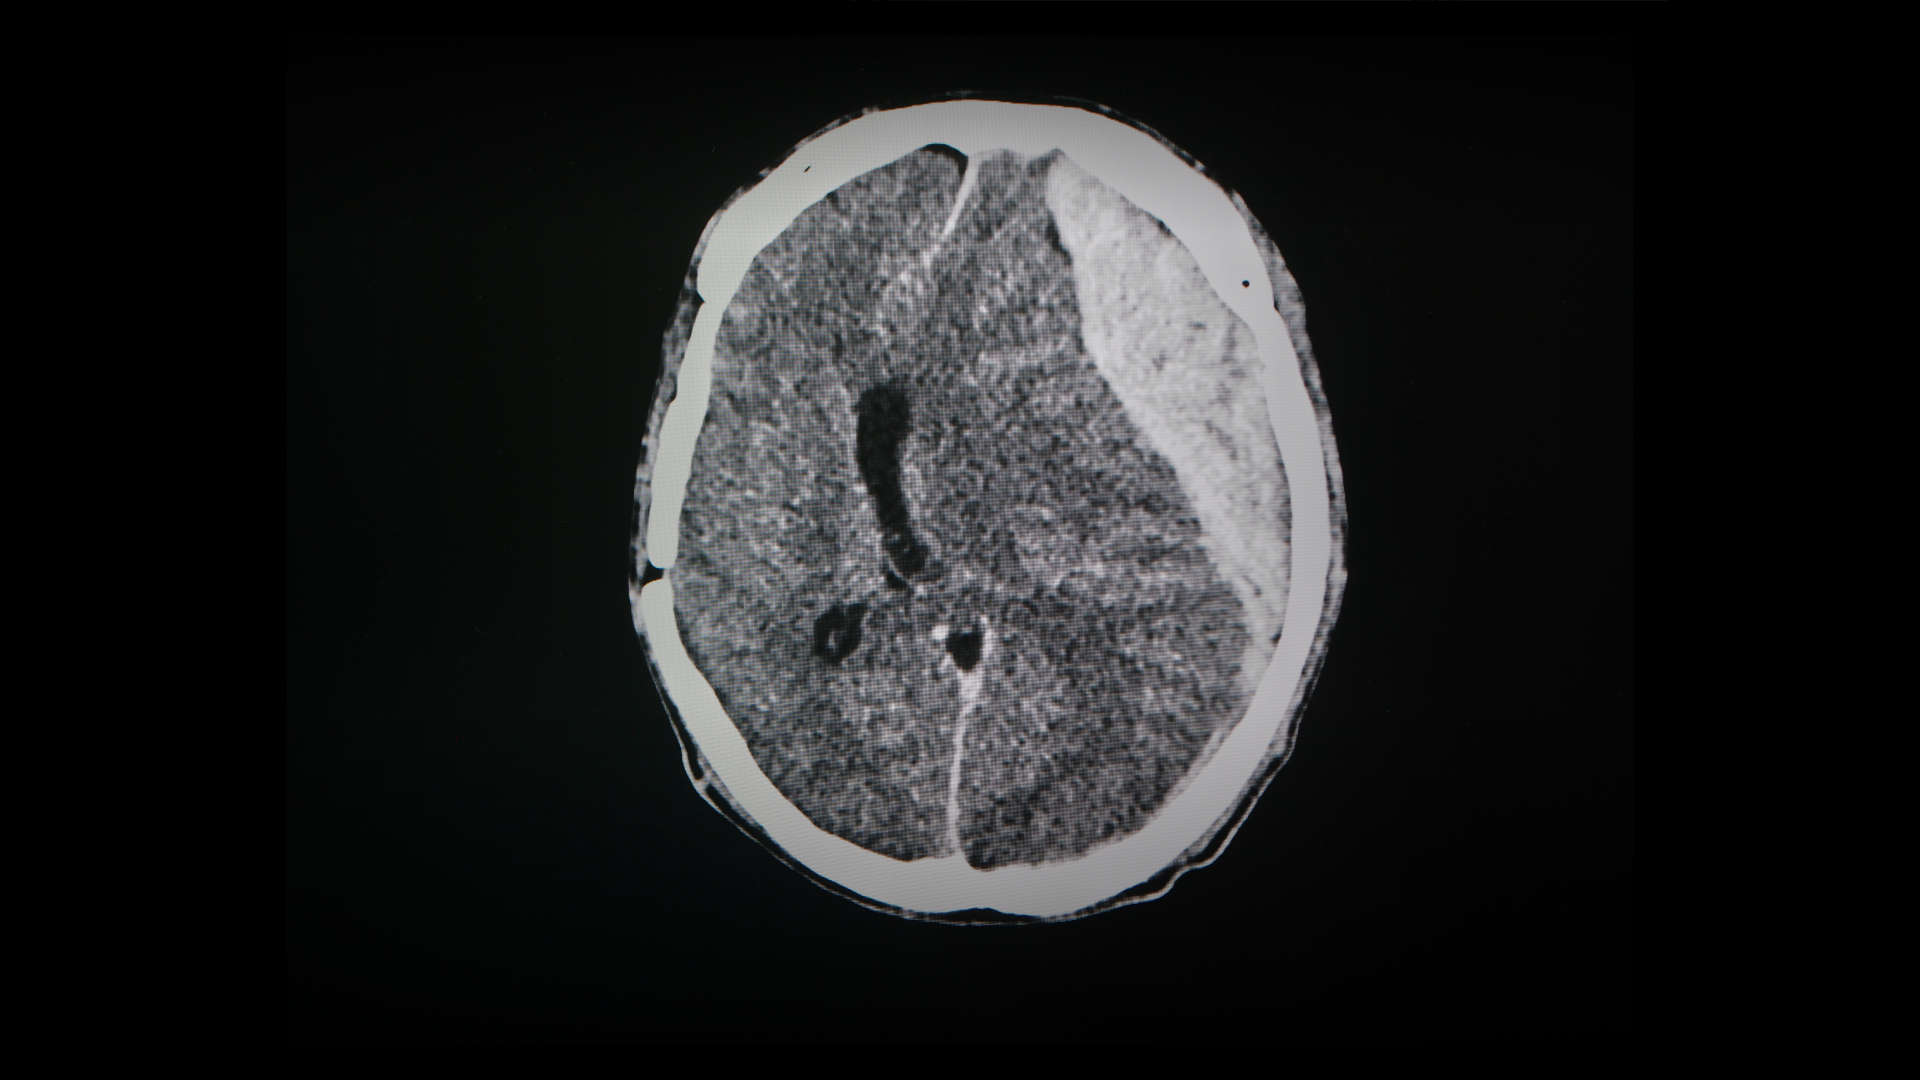

- Adults with severe TBI managed in ICU with invasive ICP monitoring and an abnormal cranial CT.

- Required sustained ICP >20 mm Hg for ≥5 minutes despite stage 1 therapy (e.g., sedation/ventilation/physiological optimisation).